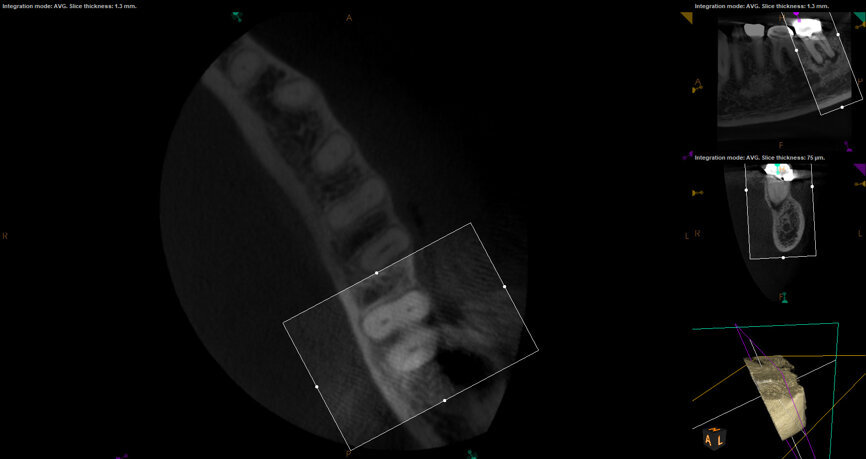

Fig. 17a: Case assisted with CBCT to determine anatomy pre-operatively. Note the multiple cross sections moving apically and the correlation to the 2-D view. Note also the conservative taper in relation to the root width. (Courtesy of Dr. Brett Gilbert)

Fig. 17b: Case assisted with CBCT to determine anatomy pre-operatively. Note the multiple cross sections moving apically and the correlation to the 2-D view. Note also the conservative taper in relation to the root width. (Courtesy of Dr. Brett Gilbert)

Fig. 17c: Case assisted with CBCT to determine anatomy pre-operatively. Note the multiple cross sections moving apically and the correlation to the 2-D view. Note also the conservative taper in relation to the root width. (Courtesy of Dr. Brett Gilbert)

Fig. 17d: Case assisted with CBCT to determine anatomy pre-operatively. Note the multiple cross sections moving apically and the correlation to the 2-D view. Note also the conservative taper in relation to the root width. (Courtesy of Dr. Brett Gilbert)

Fig. 17e: Case assisted with CBCT to determine anatomy pre-operatively. Note the multiple cross sections moving apically and the correlation to the 2-D view. Note also the conservative taper in relation to the root width. (Courtesy of Dr. Brett Gilbert)

Fig. 17f: Case assisted with CBCT to determine anatomy pre-operatively. Note the multiple cross sections moving apically and the correlation to the 2-D view. Note also the conservative taper in relation to the root width. (Courtesy of Dr. Brett Gilbert)

Managing complex anatomy is much simpler if the clinician has a pre-operative road map. The CBCT provides the roadmap and the surgical microscope the lens (literally) through which to visualize the result. Aside from a relaxed patient who is profoundly numb, being able to visualize anatomy by taking a pre-operative (and possibly intra-operative) CBCT and using a surgical microscope during treatment have no substitutes. They are the current “Gold Standard” in that 3-D imaging shows the clinician the true reality of a clinical situation as opposed to the suggestion gained from a 2-D radiograph. Proper interpretation of imaging prior to and/or during endodontic treatment goes a long way in taking the “guesswork” out of identifying canal location and other anatomical complexities as the procedure unfolds. In a 2014 study by El Fayad and Johnson, it was determined that when having a pre-operative CBCT as compared to 2-D radiographs alone, the treatment plan was modified 62 percent of the time. This is a huge game changer to think that the information learned from 3-D imaging changed the plan of treatment over six times out of 10 (Fig. 4).[2]